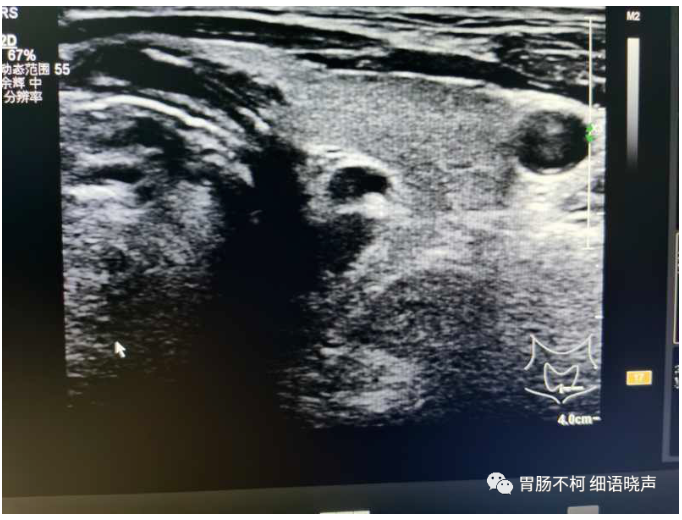

病例一:甲状腺左叶后方低回声型咽食管Killian-Jamieson憩室。

其后方与食管相通。

吞咽口水实验可见团块状强回声涌入。